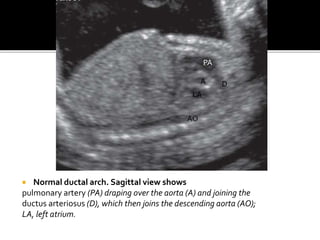

 Normal ductal arch. Sagittal view shows

pulmonary artery (PA) draping over the aorta (A) and joining the

ductus arteriosus (D), which then joins the descending aorta (AO);

LA, left atrium.

 Normal ductalarch. Sagittal view shows pulmonary artery (PA) draping over the aorta (A) and joining the ductus arteriosus (D), which then joins the descending aorta (AO); LA, left atrium. PA DA LA AO